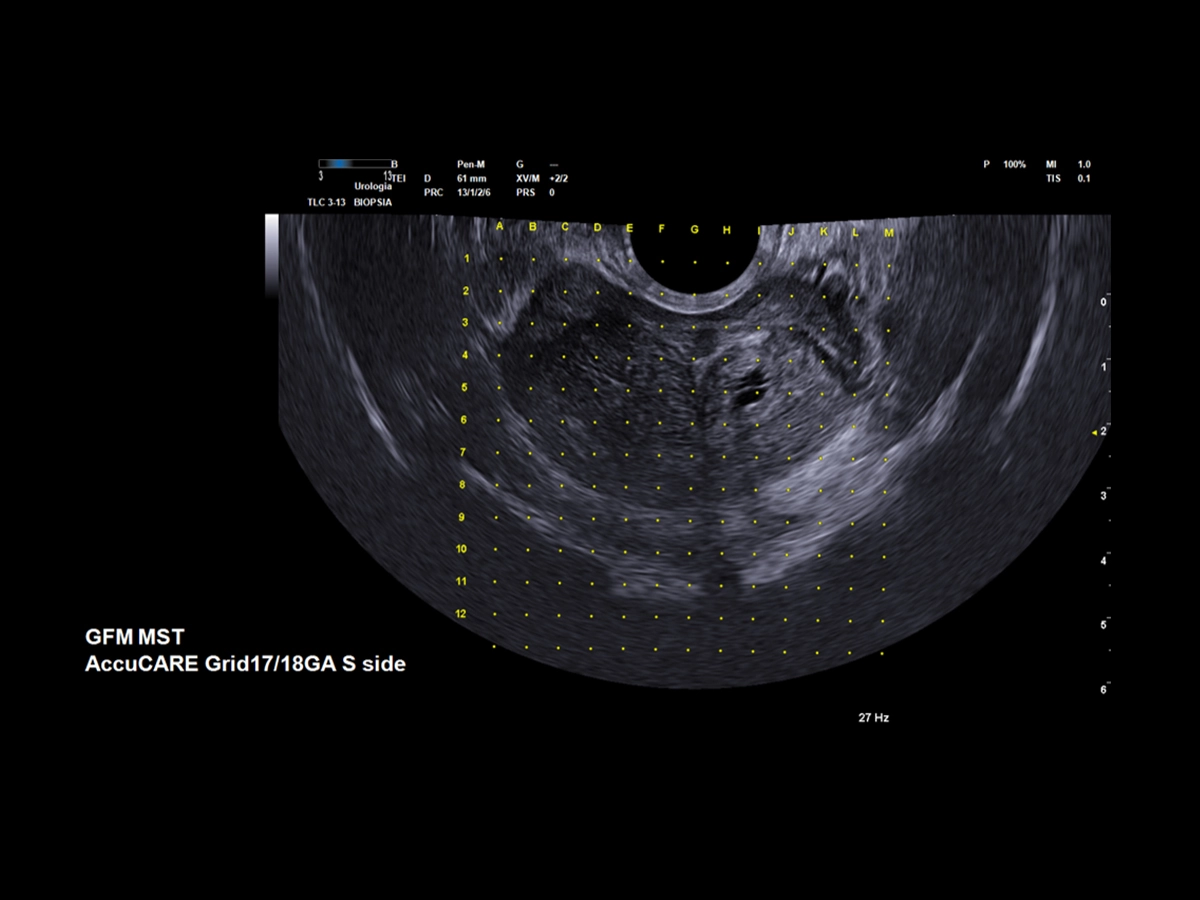

The Esaote Urology package supports the CIVCO & GfM Steppers (*), which enables precise transperineal (TPUS) biopsy procedures and targeted treatment of focal lesions.

The steppers are also compatible with UroFusion, allowing for full targeted treatment by using:

- the biopsy fusion procedure prior to treatment, which combines the core position and histopathology of the target areas to be treated (recorded on the report with sample mapping and 3D reconstruction)

- and/or mpMRI guidance, which identifies the suspicious areas.